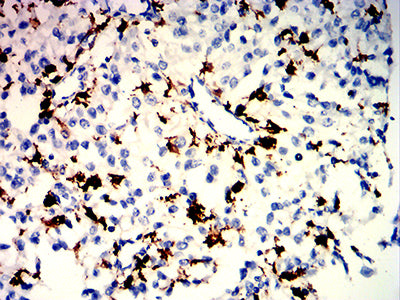

分类: 科研抗体货号: 32186别名: PTA1; DNAM1; DNAM-1; TLiSA1应用: IHC,FCM反应种属: Human

分类: 科研抗体货号: 32185别名: PTA1; DNAM1; DNAM-1; TLiSA1应用: IHC,FCM反应种属: Human

分类: 科研抗体货号: 32216别名: FRA应用: IHC,FCM反应种属: Human